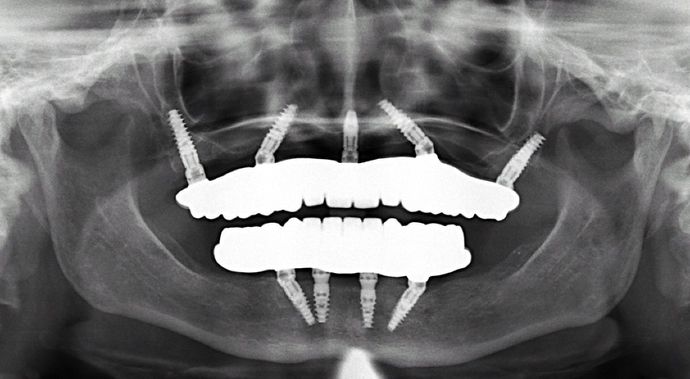

All-on-4/ Full Mouth Dental Implants / Teeth in a Day: Case 2-MS- Upper and lower All-on-4 bridges

Procedures : extractions, implants, All on 4 , Teeth in a day, no bone grafting and full mouth reconstruction with monolithic zirconia bridges.